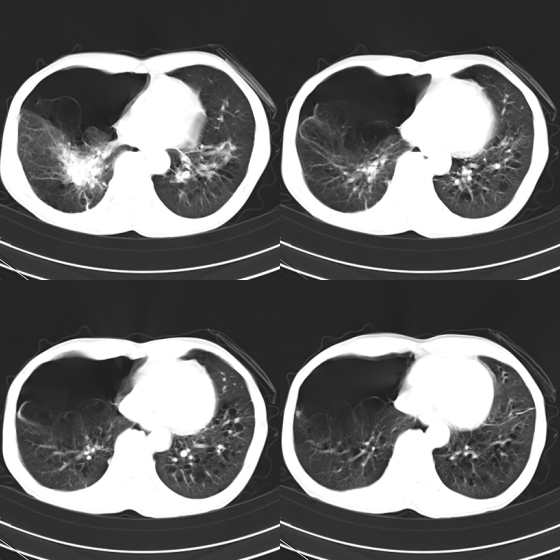

标题: CT21797:M65y,矽肺团块内空洞?

m65y,咳嗽、咯痰,煤工工作史10+年。低热,无明显脓臭痰。临床怀疑tb。

矽肺伴结核 右侧气胸,左肺上叶肺大泡

我也明知故犯一次!1、矽肺伴结核, 右下病变不排除瘢痕癌;2、慢支、肺气肿、多发肺大泡并气胸。

煤工尘肺结节易液化坏死,形成空洞,如合并结核形成空洞,周围应该有播散灶。

矽肺伴结核(左肺上叶病灶内空洞形成),右侧气胸,两肺多发性肺大泡。

、矽肺伴结核同时合并感染, 右下病变不排除瘢痕癌;2、慢支、肺气肿、多发肺大泡并气胸。

告病重没有?这种气胸不易复张,咳嗽剧烈左肺大泡再破就难活了。煤尘肺常继发结核,影像学不易鉴别。有结核的可疑临床症状,ppd5u皮试阳性,特别是强阳性,就有诊断性抗痨治疗指针。不过排他性诊断是最重要的。左上空洞内液平就不是结核应有的。同意9楼楼主看法,同时注意合并感染的问题,抗炎覆盖广一点。